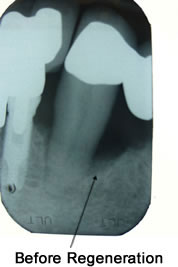

Bone and Tissue Regeneration

When the damage caused by Periodontal Disease is significant, a Bone and Tissue Regeneration procedure may be necessary to save your teeth.

During this treatment, Dr. Zavoral gently folds back the gum and removes the disease-causing bacteria and infection. She will then place membranes, bone grafts and tissue-stimulating proteins to help your body naturally heal and regenerate bone and tissue.

Regeneration of the bone and tissue, along with a strict home care program and increased professional cleanings, will greatly increase your chances of keeping your natural teeth.